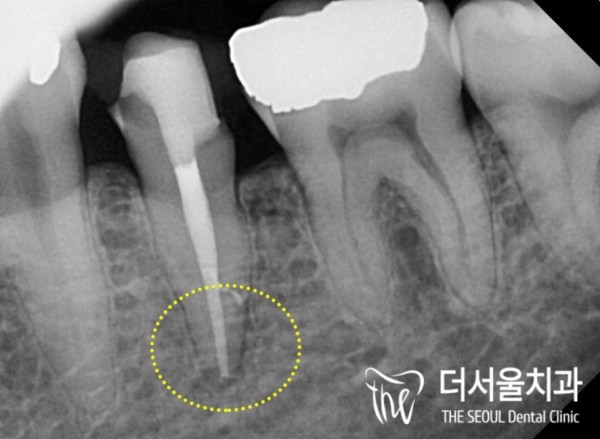

아말감 보철 밑으로 2차 충치가 생긴 모습이 확인됩니다.

치료 받은 곳에 다시 충치가 생기는것을 2차 충치라고 합니다.

이미 법랑질과 상아질을 뚫고 치수까지 감염이 일어난 상태로

통증이 많이 느껴지는 상태였습니다.

Secondary cavities are confirmed under the amalgam prosthesis.

The recurrence of cavities in the treated area is called secondary cavities.

It's already been infected through enamel and dentine to the pulp

I felt a lot of pain.